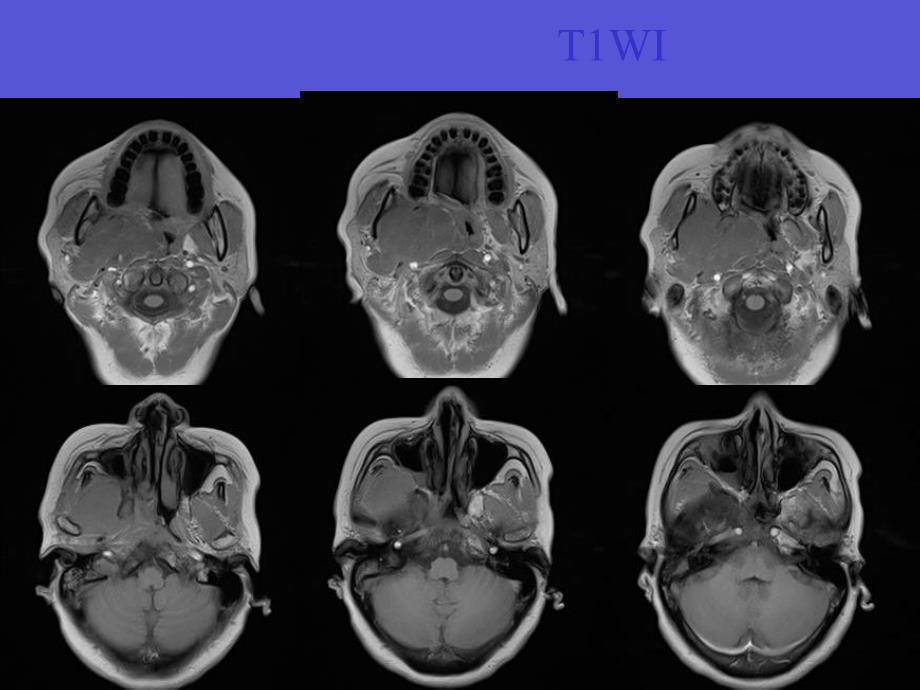

1、病例1患者女,58岁,口咽异物感,吞咽不畅,右颈部疼痛不适2个月无发热、盗汗及体重减轻,无咳嗽、咳痰,无明确既往病史查体:右软腭膨隆,口咽腔缩小,右颌面部肌肉略压痛鼻咽镜:鼻咽部右侧可见粘膜膨隆突出,右侧软腭膨隆 T2WIT1WIFS-T2WIGd-TraGd-SagGd-CorCT病理结果孤立性纤维性肿瘤,浸润生长,累计横纹肌组织孤立性纤维性肿瘤 孤立性纤维性肿瘤由(solitary fibrous tumor,SFT)由Klemperer和Rabin于1931年首先在胸膜发现并命名 SFT 是一种起源于CD34 阳性的树突状间叶细胞的肿瘤,并具有向纤维母细胞、肌纤维母细胞分化的特征 胸膜以

3、其临床症状差异很大,早期常表现为毫无临床症状的缓慢增大的肿块。临床上多数病例为缓慢生长的无痛性包块;特殊部位者可有相应压迫症状,少数直径较大者可产生副肿瘤综合症影像学特点 SFT CT平扫表现为边界清楚、密度均匀、与周围软组织等密度的孤立性软组织肿块;无分叶或可见浅小分叶;一般肿块内部无钙化;邻近骨结构无明显的骨质破坏;增强扫描实质一般明显强化 CT上明显的骨质破坏则反映了病变有恶性生物学行为 SFT 在MRI 上表现为T1WI 上以低信号为主,T2WI 上为低或中低混杂信号为主,增强后不均匀强化 其信号改变与病理成分相对应,SFT 瘤体内常含有丰富的纤维组织、透明样变性、黏液样变性、囊性变及

4、出血等,黏液样变或囊变坏死区呈高信号,细胞密集区呈稍高信号,低信号区反映致密胶原纤维鉴别诊断1、鼻咽癌 鼻咽癌是源于鼻咽部上皮组织的一种恶性肿瘤 大多于4060岁发病,男多于女,血涕是最常见的早期症状 NPC好发于鼻咽部侧隐窝的黏膜表层,使局部黏膜增厚或形成小肿块,至鼻咽腔不对称变浅、变窄。肿瘤组织的信号强度较均匀,T1WI 呈较肌肉略低信号,T2WI 呈略高信号,Gd-DTPA 增强后肿块明显强化。部分可呈肿块样突入鼻咽腔,或向黏膜下生长突入咽旁间隙的内后方;部分可呈浸润性生长,肿瘤与周围结构分界不清,脂肪间隔消失,局部骨质可有破坏 NPC可早期发生淋巴结转移,甚至鼻咽部的肿瘤处于影像学和鼻